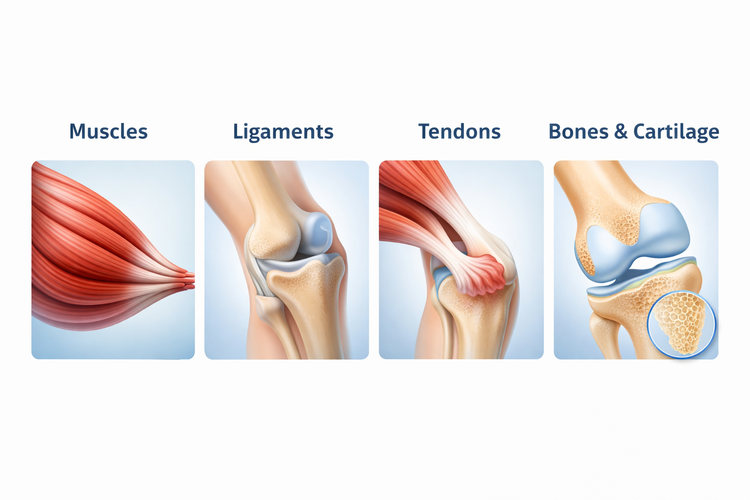

Sagittal MRI scan of a knee used to diagnose sports injuries.

1. Clinical history – Understanding how the injury occurred, the symptoms experienced, and any previous injuries helps narrow down the likely diagnosis

2. Physical examination – Testing the affected area for swelling, tenderness, range of motion, strength, and joint stability. Specific clinical tests, such as the Lachman test for ACL injuries or the anterior drawer test for ankle sprains, can help identify which structure is involved

3. Imaging – X-rays are used to check for fractures, while MRI provides detailed views of soft tissues such as ligaments, tendons, and cartilage. Ultrasound may also be used for tendon and muscle injuries

The type and extent of imaging depends on the clinical findings. Not every injury requires advanced imaging, and the clinical examination often provides enough information to guide initial treatment.